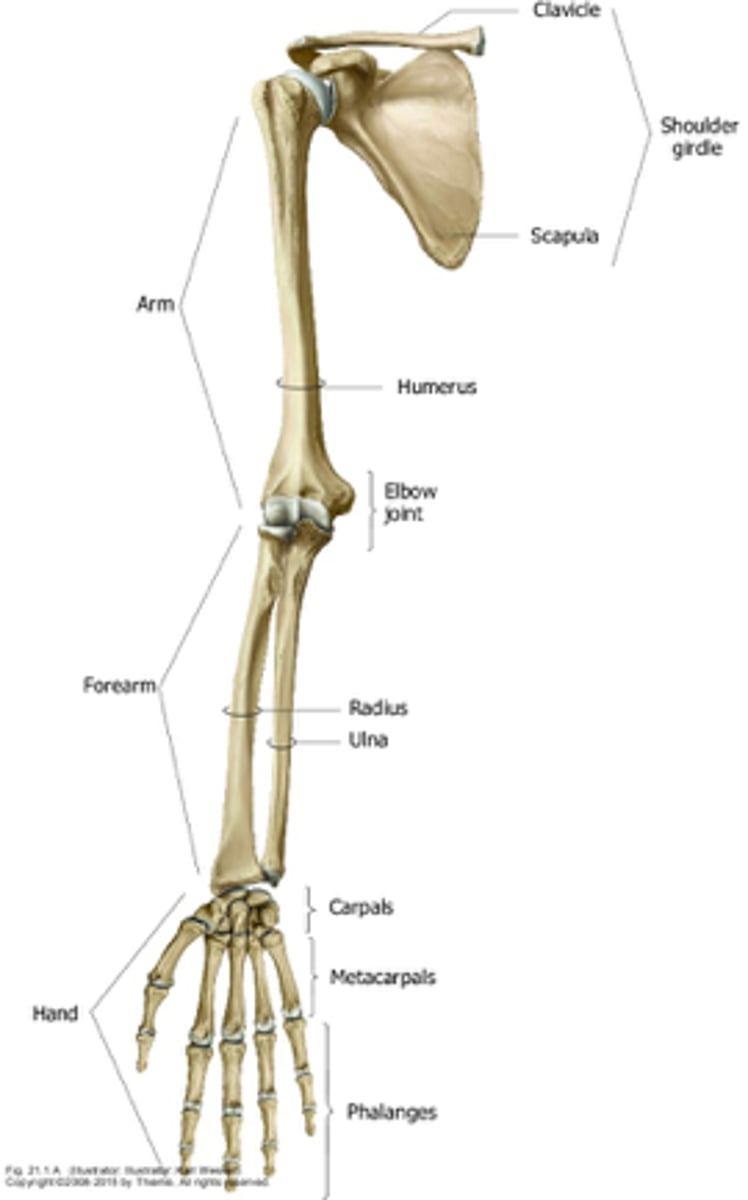

What are the anatomical divisions of the upper extremities?

- shoulder

- arm

- forearm

- hand

Overview of the Arm:

- 1st segment and longest part of the free upper limb

- extends between and connects the shoulder and elbow

Overview of the forearm:

- 2nd segment and second lomgest portion of the UL

- extends between and connects the elbow and the wrist

Overview of the hand:

- most distal

What parts consist of the hand?

- wrist

- palm

- dorsum of hand

- digits

The humerus is the ______ bone in the UE

largest

What bones do the humerus articulate with?

- scapula via glenohumeral joint

- radius & ulna via elbow joint

Bones of the forearm:

radius and ulna